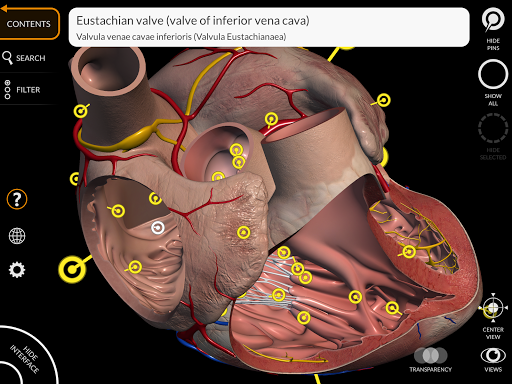

يتيح لك "Anatomy 3D Atlas" دراسة التشريح البشري بطريقة سهلة وتفاعلية.

من خلال واجهة بسيطة وبديهية، من الممكن ملاحظة كل بنية تشريحية من أي زاوية.

تتميز النماذج التشريحية ثلاثية الأبعاد بتفاصيل خاصة ودقة تصل إلى 4K.

• الجهاز القلبي الوعائي

• وظيفة الإشارة المرجعية لحفظ وجهات النظر المخصصة

• الدوران الذكي الذي يحرك مركز الدوران تلقائيًا

• من خلال تحديد نموذج أو دبوس، يظهر المصطلح التشريحي ذي الصلة

• وصف العضلات: الأصل والإدخال والتعصيب والعمل